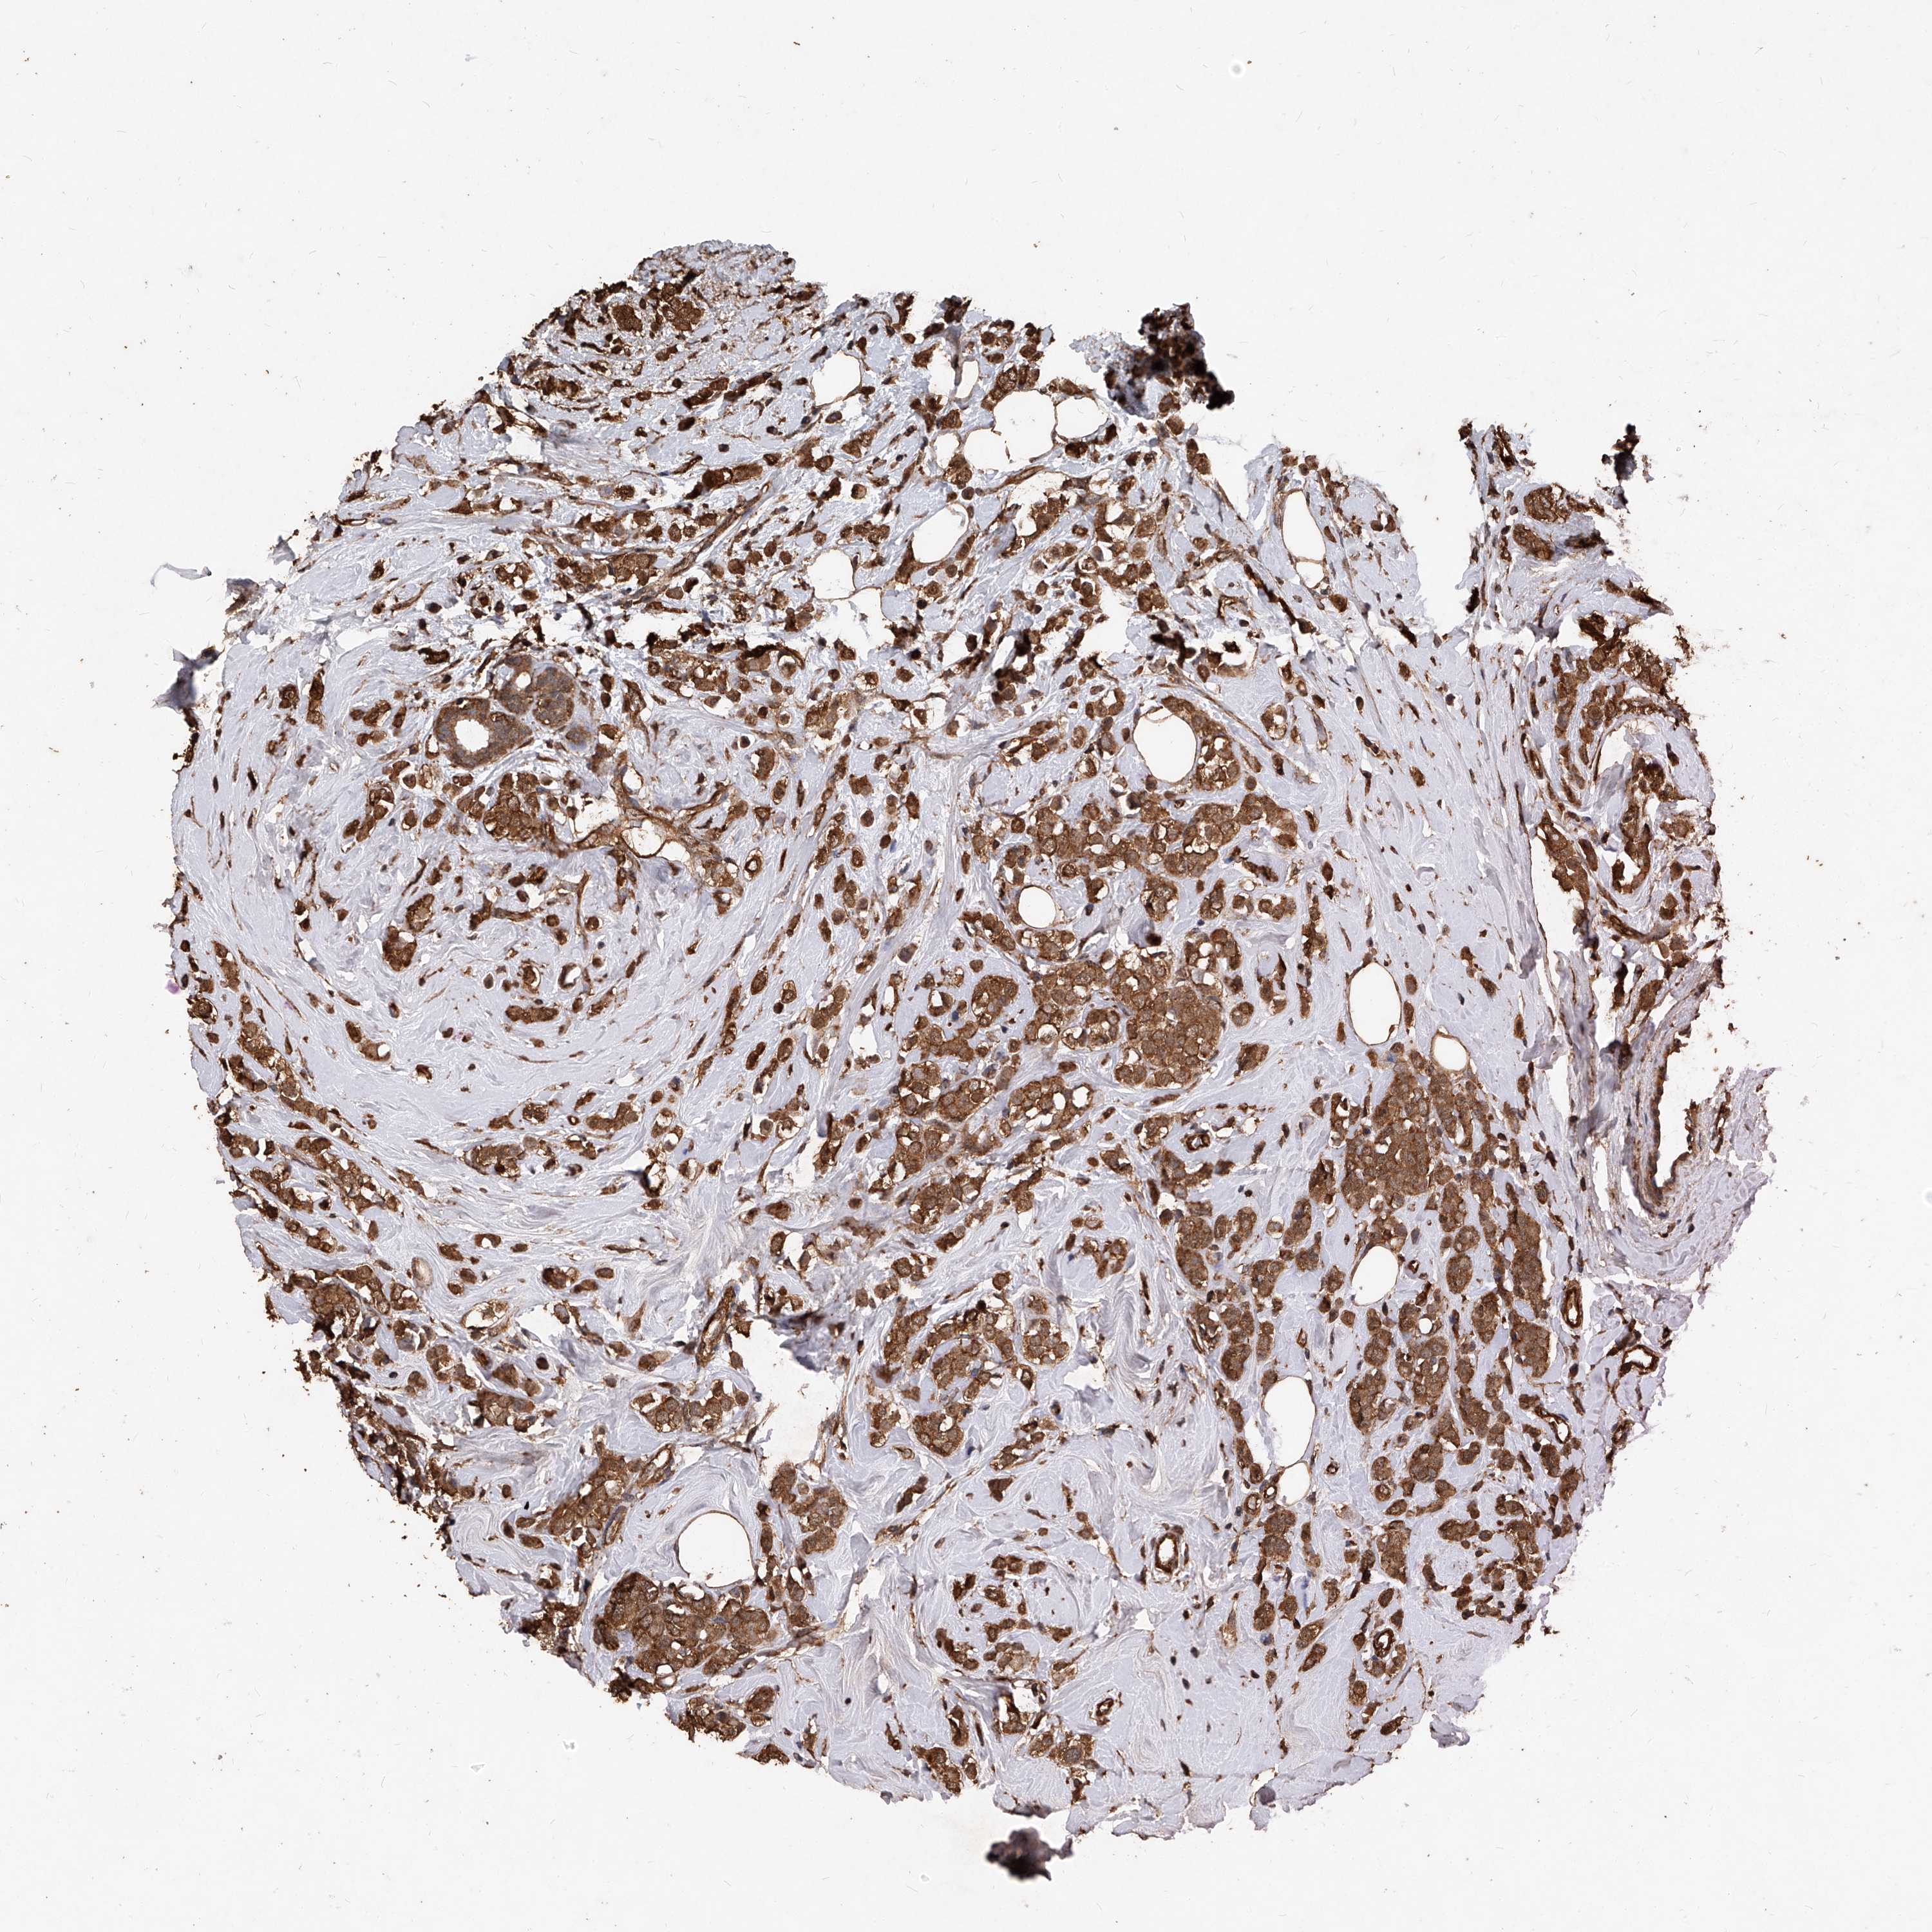

CANCER BREAST CANCER Show tissue menu

BRCA TCGA BRCA VALIDATION PROTEIN EXPRESSION

Breast cancer

Human cancer